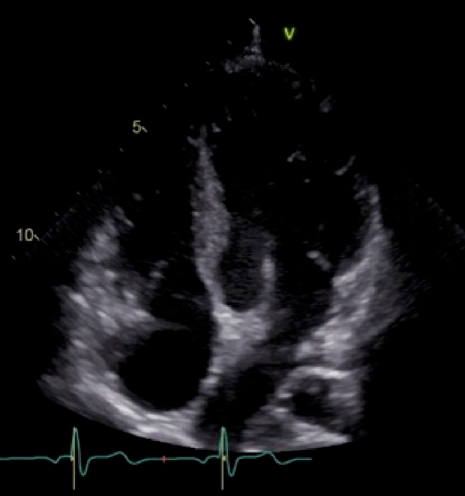

Fig. 3 A four-chamber view at the latest investigation on echocardiography

Right and left ventricular cavities are balanced in size.